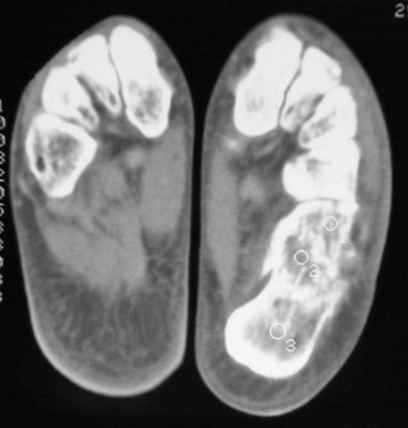

Уважаемые коллеги! Пришел на консультацию больной - "растяжение связок левого голеностопного сустава" полтора месяца назад, поскольку был в морях, на ногу не наступал. Снимки и КТ - в приложении.

Как бы кто лечил с учетом времени после травмы - 52 дня? Человек физического труда. Социальные запросы самого больного высокие, плюс медкомиссии перед рейсами - с хромотой нельзя!

Целесообразно Вашему пациенту выполнить подтаранный компрессионный расклинивающий артродез с использованием канюлированных винтов.

52 дня - неудобный срок, особенно учитывая недостаточную нагрузку ноги в плавании. Я обычно пациентам в такой ситуации назначаю препараты кальция и дозированную нагрузку, через 1-1,5 месяца после - оперируем. Операция показана для восстановления оси и высоты пяточной кости, устранения грушевидного расширения ее и вальгусного отклонения,устранения болевого и посттромботического синдромов. Тему лечения осложненных переломов пяточной кости в поздние сроки не освещал в известной Вам монографии сознательно: это одна из глав диссертации моего ученика С.М.Платонова.